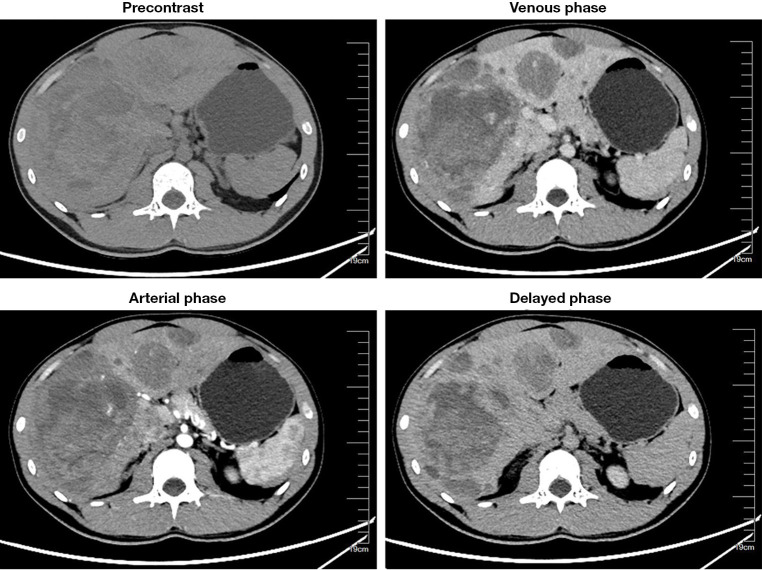

Case description: In the present report, a young male presented with right upper quadrant abdominal pain and hemoperitoneum was eventually diagnosed as hepatic angiosarcoma based on the immunohistochemical staining results of a liver needle biopsy. Contrast-enhanced ultrasound (CEUS) effectively improved the accuracy of the liver needle biopsy in this case. This report describes the epidemiology, presentation, laboratory tests, imaging findings, and pathological features of a rare hepatic angiosarcoma seen in this young male. The patient rapidly developed severe abdominal hemorrhage. Transcatheter hepatic artery embolization, blood transfusions, and symptomatic treatments were administered. The family members abandoned treatment because the patient was in critical condition and could not receive antitumor therapy.

Conclusions: This case emphasizes the significance of pathological findings in the diagnosis of PHA especially in non-high-risk individuals, and the supportive role of CEUS in guiding the liver needle biopsy. Abdominal hemorrhage is one of the serious complications of PHA and transarterial embolization (TAE) should be considered for controlling life-threatening bleeding from ruptured tumor. Further investigation is required to early diagnosis and to improve the prognosis of patients with PHA.